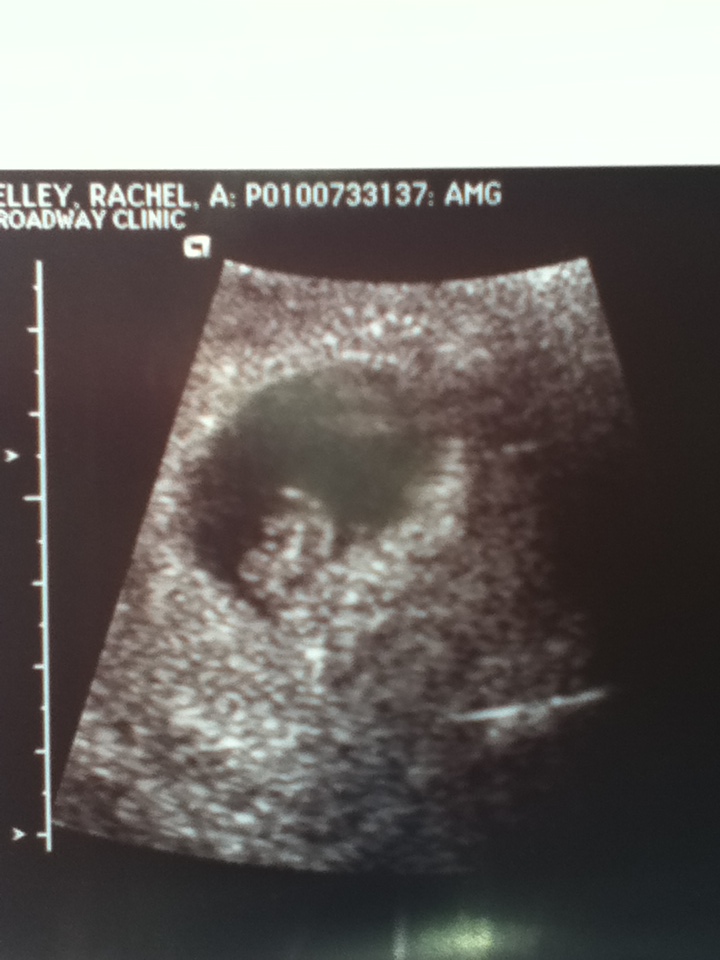

So that brings us to Monday. Yaay ultrasound day. My hubby and I got to the doc about 8:45 for a 9am ultrasound appt. Its was a mostly happy appt, but there was a small amount of sadness, but overall lots of happiness. Let me explain, I'm laying there on the table goo on my belly me staring at the monitor. And I say to the ultrasound tech "there was two sacs at my last appt on the unofficial ultrasound" and she looks at me and replys "hmm oh, those are the things they don't tell me" fallowed by silence. So the little but of sadness was that one of the sacs is no longer in there... but the AMAZING news is that we have one healthy baby with an amazing heartbeat of 156. It was so awesome to see the little flicker of the heartbeat... just amazing. I was 8 weeks 3 days at my appt and baby measured a little small at 7 weeks 4 days, but I know that's ok, we'll catch up.

| my little bean, oh how I love you already. |